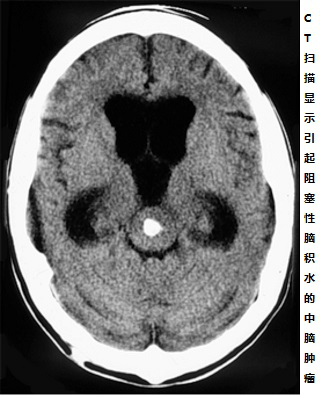

中脑胶质瘤被认为“可能是人体内较少导致病人死亡的肿瘤”,患者死亡多是由于肿瘤引起的阻塞性脑积水,而不是肿瘤本身。患者表现出的脑积水的症状和体征可能包括:恶心、呕吐、易怒、头痛、视线模糊、嗜睡、癫痫。

磁共振成像(MRI)是诊断中脑肿瘤的优选方法。磁共振成像的引入,提高了诊断的准确性。磁共振成像能够识别重要的影像学特征和肿瘤的多平面定位。它允许在大多数情况下精确评估肿瘤生长模式和准确的术前诊断。同样,术后MRI显示出切除的放射效果,区分残留和复发的肿瘤以及显示肿瘤的变化[2]。功能成像如质子磁共振波谱是区分低级别和高级别胶质瘤的合适工具。